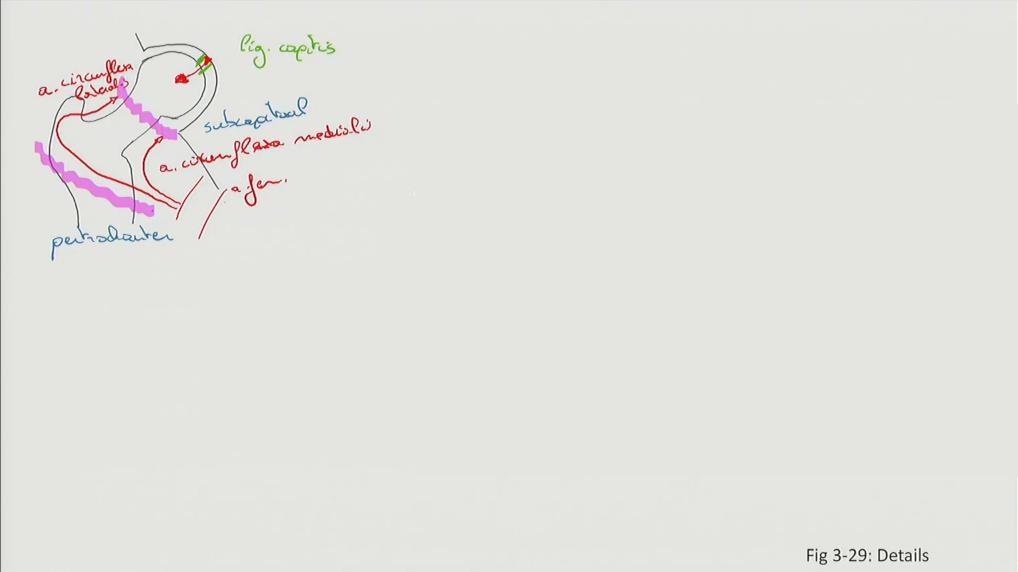

Fig 3.29b1: Details - femur